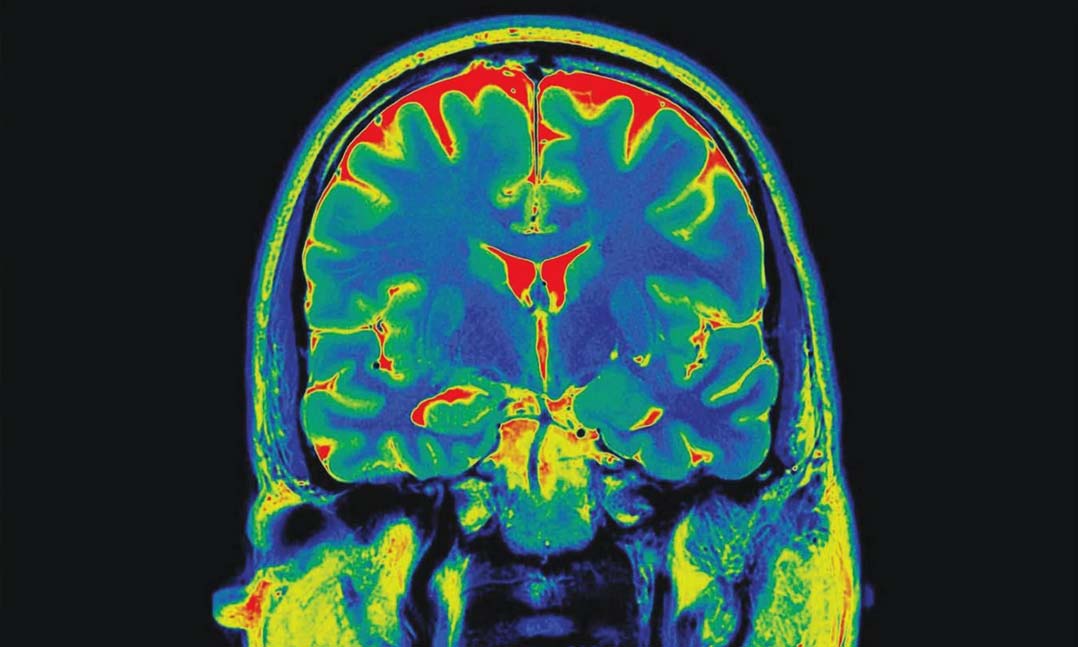

Brain scanTo research, scientists from the VA Connecticut Healthcare System, Icahn School of Medicine at Mount Sinai, Israel’s Ben-Gurion University of the Negev and the Yale University School of Medicine observed brain activities of 28 people — 11 women and 17 men — with an average age of 38. PTSD patients shared three types of memories:

Researchers turned each patient’s recollection into an audio script narrated by another person. Patients received an MRI while presented with a summary of their own experiences. Scientists observed that the PTSD patients experienced “traumatic” memories in a different part of the brain than “sad” and “calm” memories.

The memories of “sad” and “calm” events, according to the study, triggered the brain’s hippocampus, which is known to play a role in long-term memory. However, researchers found that during the re-experiencing of traumatic events, the posterior cingulate cortex (PCC) was stimulated in the patients’ brains.